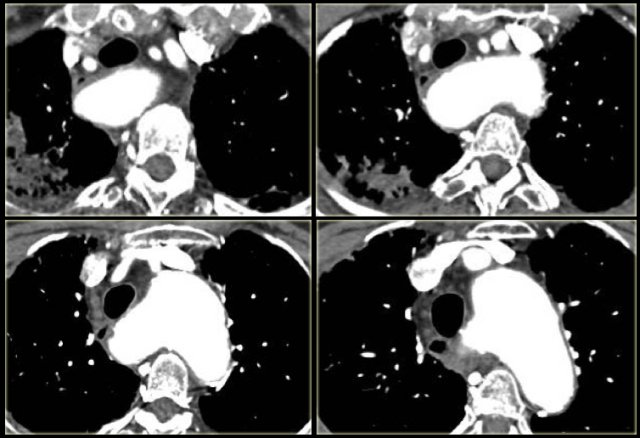

On the left axial images and posterior view of volume rendered reconstruction.

Describe the findings and then continue.

The findings are:

1. four vessel sign

2. double arch

3. right arch higher and larger

4. esophagus and trachea are completely encircled

The narrowing of the trachea is seen on the axial images, but better appreciated on the MPR and Volume Rendered image.